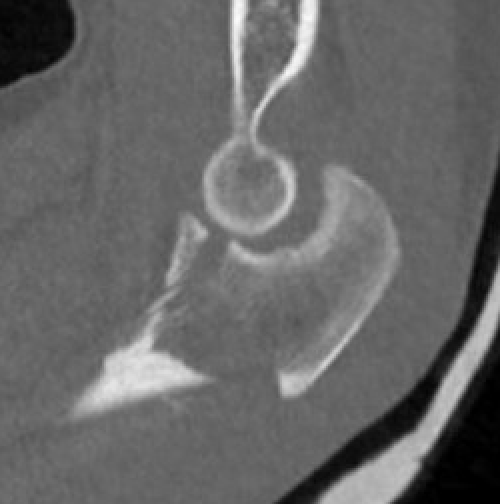

Elbow dislocation + olecranon fracture + radial head/neck fracture +/- coronoid fracture

Olecranon plate + ORIF Type II coronoid process + radial head replacement

Olecranon plate + medial coronoid buttress plate + radial head replacement

Complex proximal ulna fracture with radial head replacement subluxation